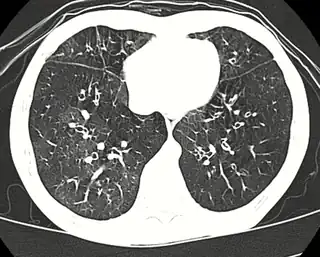

![]() Tomografía computada de alta resolución mostrando una bronquiolitis obliterante con atenuación en mosaico, broquiectasias, atrapamiento aéreo y engrosamiento bronquial[2] | ||